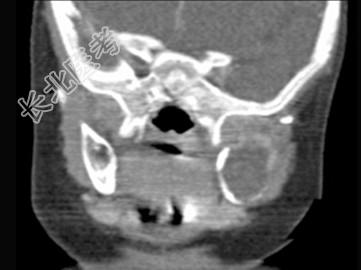

- 单项选择题男,2岁, 左侧颜面部、右肩部肿块,疼痛, 结合图像,最可能的诊断是 ( )

A、骨结核

B、骨髓炎

C、骨嗜酸性肉芽肿

D、骨囊肿

E、骨肉瘤